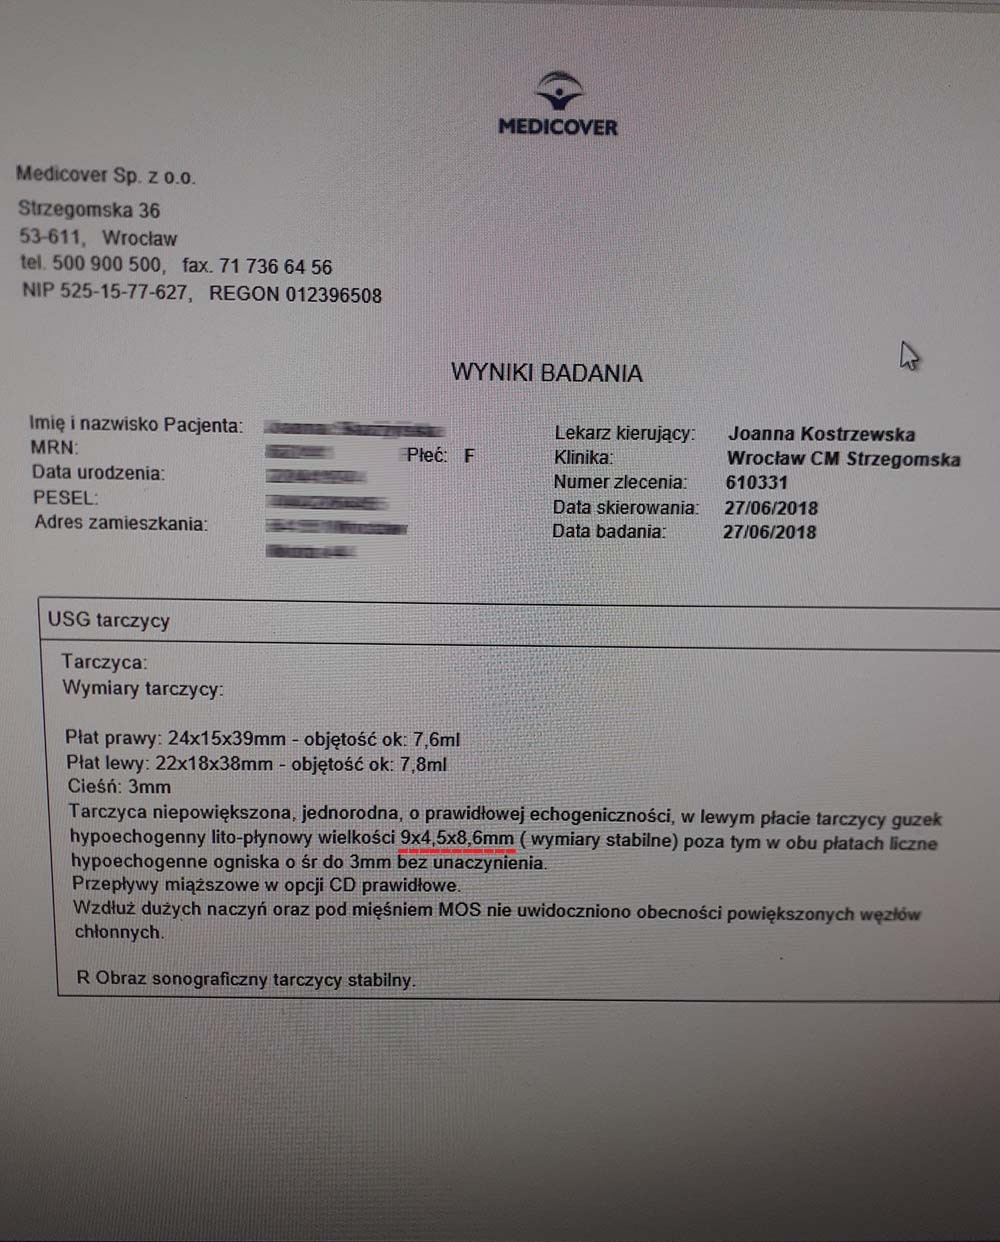

EFEKT PREPARATU PRZY GUZKACH NA TARCZYCY

Przypadek kobiety lat 46, przed podaniem preparatu wykryto guzki na tarczycy o wymiarach 9x4 mm i 5x8 mm, po zaledwie miesiącu stosowania bez dodatkowej farmakologii guzki zmniejszyły się do rozmiarów 7x4 mm i 5x3 mm. Szybka redukcja guzków (~20-65% ) bez ingerencji chirurgicznej i farmakologicznej wskazuje na naprawę komórkową na poziomie mitochondrialnym, co zapobiega nieprawidłowym podziałom komórkowym i rozwoju guzów. Preparat zwiększa wydajność mitochondriów do produkcji ATP, stymulując apoptozę uszkodzonych komórek, jednocześnie wpływając na regenerację i tworzenie poprawnych struktur. Jest to szczególnie wartościowe w przypadku guzów łagodnych, gdzie standardową procedurą jest jedynie obserwacja zmian, co najczęściej prowadzi do rozwoju znacznie trudniejszych do opanowania nieprawidłowości.